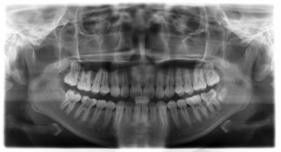

臨床診斷:通過3D數(shù)字化全景機(jī)的檢查,患者的上牙前突屬于牙性,非骨性問題,雙唇閉合時(shí)可見明顯隆起,X片顯示根尖無異常,上下后牙存在間隙,可通過美國MBT直弓絲正畸技術(shù)將其矯正復(fù)位,收攏間隙,矯正所需時(shí)間一年半左右。

全景機(jī)正位片